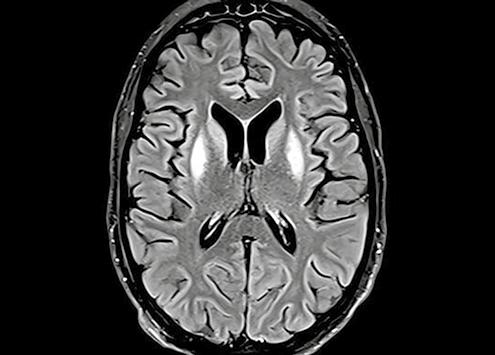

In early 2022, shortly after the outbreak of the war between Russia and Ukraine, 18-year-old Anna Kuzma developed a temperature, which quickly spread throughout her body, causing severe convulsions and a brain infection.

Acombined mission ensued, involving Hatzolah Air and Zaka with medical support provided by the Trauma team from Shaare Zedek to get Anna safely to Israel for treatment. Anna arrived at Shaare Zedek and was admitted to the Helmsley Neurological Institute with her condition identified as extremely critical. Doctors feared she had limited chances of survival.

Over the coming weeks and months, she was treated with an innovative approach under the care of Dr Stefan Mausbach, Director of our Neurological Intensive Care Unit and Dr Roni Eichel, Director of the Department of Neurology. Dr Mausbach explains, “In Ukraine Anna developed a fever and was treated by a family doctor. After a week she lost consciousness and started to experience convulsions. When she arrived at Shaare Zedek we carried out a procedure

under deep anaesthesia to lower the brain activity and stop the convulsions.”

For three months, Anna remained at Shaare Zedek in serious condition. Dr Mausbach and his team were convinced the outcome was not going to be good. “When I received the brain MRI, I said to myself there is no way she will survive this. The damage was so significant, usually it’s something from which there is no way back.” However, to everyone’s amazement, slowly but surely Anna’s condition started to stabilize.

When Anna arrived at Shaare Zedek all the imaging scans indicated doctors were treating a young woman who was nearing the end of her life. Dr Roni Eichel shared, “At first, our impressions were that we would not be able to save her. This was a rare case of a medical condition – a febrile illness that quickly develops into epilepsy that is difficult to treat. In most

cases the patient suffers severe brain damage and, in many cases, there is a risk of death”.

Despite those initial deep concerns, the medical teams never gave up and used intensive care approaches which had never been used in Israel before. This dedication led to what many would have thought the unthinkable. Three months later, Anna regained full consciousness and a high level of overall functioning and was able to be discharged from hospital. A story of hope, triumph and great pride to all who were involved in her care.